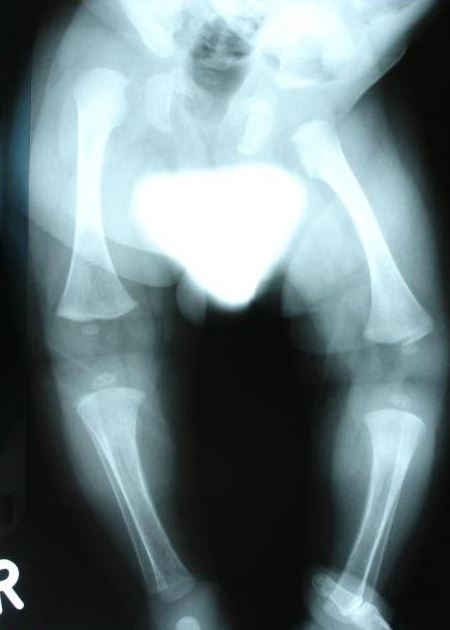

دىياگنوز قويۇش ئاساسلىقى كلىنىكىلىق كۆزىتىش ۋە رېنتگېن نۇرىدا تەكشۈرۈشكە تايىنىدۇ. رېنتگېن كۆرۈنۈشىدە سۆڭەكلەرنىڭ شەكلى ئۆزگىرىشى ۋە سۆڭەك پەردىسىنىڭ قېلىنلىشىشى كۆرۈنەرلىك بولىدۇ. ئەڭ ئاخىرقى دىياگنوز گېن تەكشۈرۈش ئارقىلىق LIFR گېنىدىكى نۇقساننى تېپىش بىلەن جەزملەشتۈرۈلىدۇ.